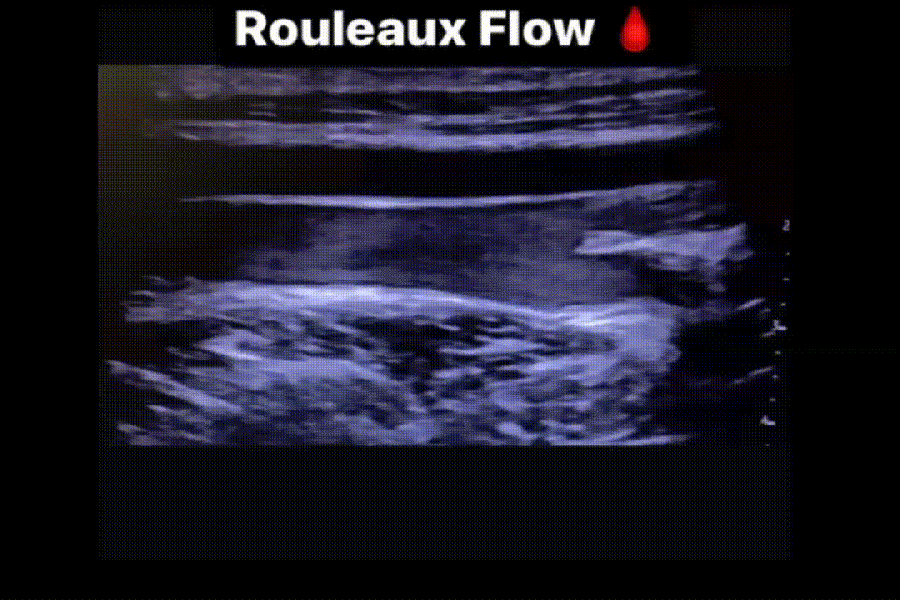

Normally Blood flow is anechoic due to the size of the RBC’s inability to reflect the sound waves. However when they aggregate or stack they become mobile reflectors. The flow is typically slow and sluggish. Compression of the vessel is still feasible and will clear the rouleaux momentarily.